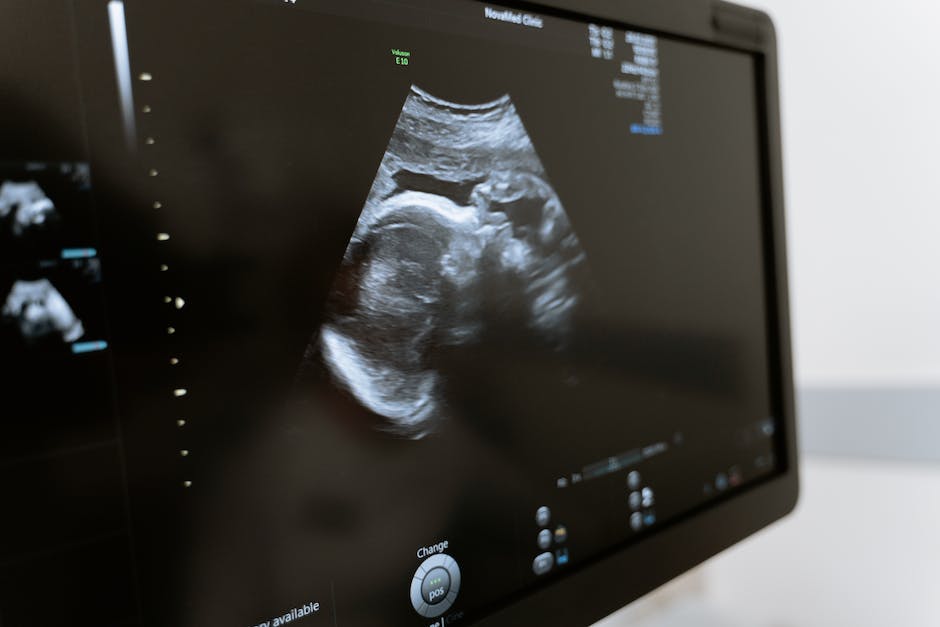

유방 초음파

유방 초음파는 소프트 티슈 이미징 기술로, 의사는 소리 파동을 사용하여 유방 내 다양한 구조를 파악할 수 있습니다. 이를 통해 종양의 크기, 위치와 같은 정보를 얻을 수 있습니다. 유방초음파는 일반적으로 매몰 검사와 함께 사용되어 추가 정보를 제공합니다.